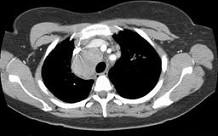

问题 女,33岁,咳嗽,乏力,低热,皮肤有结节,结合CT图像,最可能的诊断是 ( )

选项 A.肺结核 B.霍奇金病 C.非霍奇金病 D.结节病 E.肺癌

答案 D